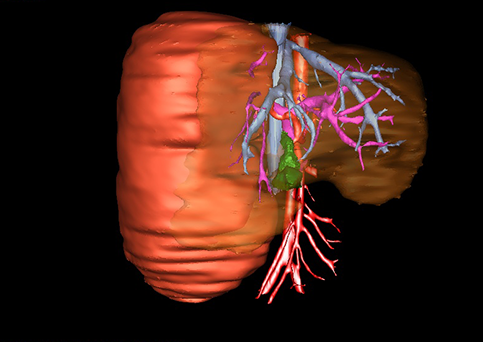

近年来由于数字医学的发展,基于可视化三维重建技术的计算机辅助手术系统极大推进了小儿肝脏肿瘤的精准手术的进步。可以立体透视肝脏解剖、精确掌握肝段的边界、精确测算肝段乃至任意血管所支配的功能体积、准确定位病灶及其与邻近血管的解剖关系,最终对不同手术方案进行比较、筛选和优化。因此,计算机辅助手术规划系统是实现精准肝切除的有力辅助工具,是未来数字外科、精准外科等21世纪外科新理念的重要技术支撑。

计算机辅助手术规划系统具有良好的操作可行性、计算准确性和三维显示效果,可半透明、交互式显示真实的肝内立体解剖关系和空间管道变异,准确计算肝内管道的直径、走行角度,两点间的垂直距离,和任意血管的支配或引流范围等传统二维影像无法获取的信息,有助于实施个体化手术,提高了手术的确定性、预见性和可控性。计算机辅助手术规划系统可直观显示预留肝脏的结构和功能,并可通过虚拟切割功能辅助术者对手术方案进行蹄选和优化,系统评估手术风险和制定对策,改变了部分二维规划的术式和切除范围,使部分二维规划认为不能切除的患者成功手术,提高了手术的根治性、安全性和病变的可切除性,更加符合精准肝脏外科的术前规划要求。详见第11章。

随着计算机技术及影像检查技术的不断发展,以精确的术前影像学和功能评估、精细的手术操作为核心的精准肝切除技术日益受到重视。基于数字医学的计算机辅助手术技术(computer-assisted surgery,CAS)则是实现肝脏精准手术操作的基础。计算机辅助手术系统(CAS)可将术前二维(two dimensional,2D)的CT/MRI影像数据进行三维(three dimensional,3D)重建,建立个体化的肝脏三维解剖模型,清晰显示肝脏内脉管系统的走行及解剖关系,还原病灶与其周围脉管结构的立体解剖构象,准确地对病变进行定位、定性和评估,制定合理、定量的手术方案,实施个体化的肝脏血管取舍分配方案及实施精准肝脏手术。一般认为CAS包括:创建虚拟的患者的图像;患者图像的分析与深度处理;诊断、手术前规划、手术步骤的模拟;术中实时导航。应用本技术后,由于可以更清晰地看出肿瘤的界限,特别是根据肝血管的显影,判断出肿瘤与门静脉及肝静脉的关系以在手术前较准确地估计出手术成功切除的可行性。以往部分根据普通强化CT判断无法手术的病例而被评估为可以成功切除并手术成功。